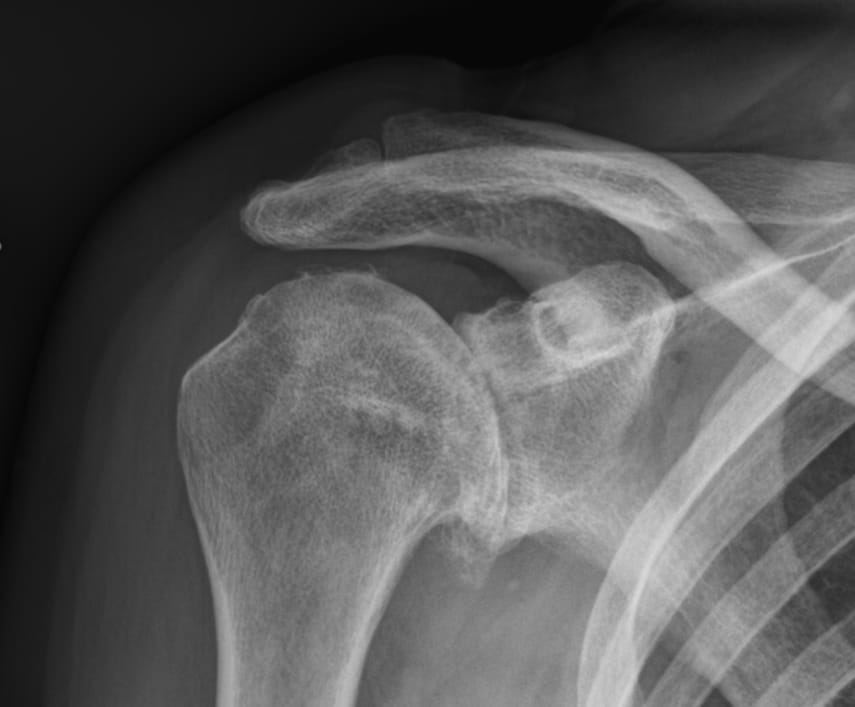

- Radiografii: Acestea pot arăta reducerea spațiului articular, prezența osteofitelor (excrescente/ciocuri osoase, constant în partea inferioară a capului humeral) sau alte modificări degenerative, printre care modificarea poziției capului humeral.

- Imagistică avansată: RMN-ul sau CT-ul pot oferi o imagine de ansamblu, detaliată a stării cartilajului, stocului osos și a structurilor înconjurătoare.